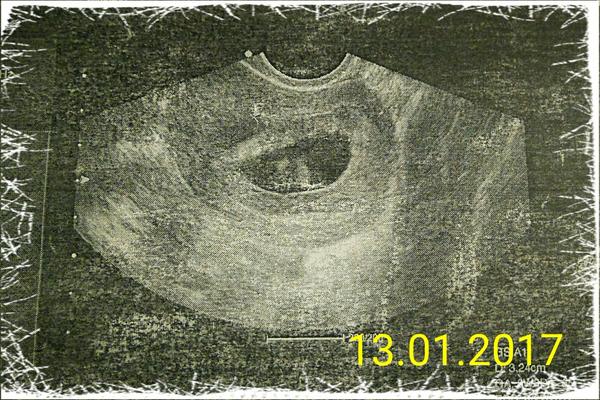

akurat na fazulke sa nam spravil skrabanec :/ no co uz